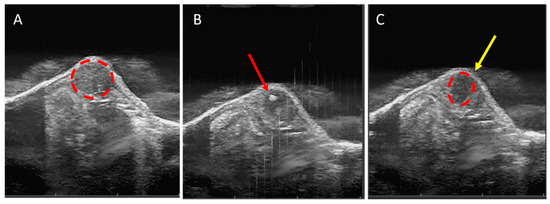

3.1. Tumor Tissue Can Be Effectively and Precisely Targeted and Ablated with Histotripsy